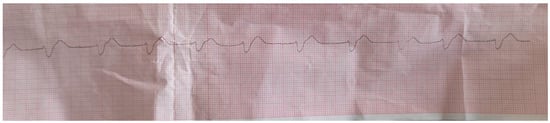

2. Case Report